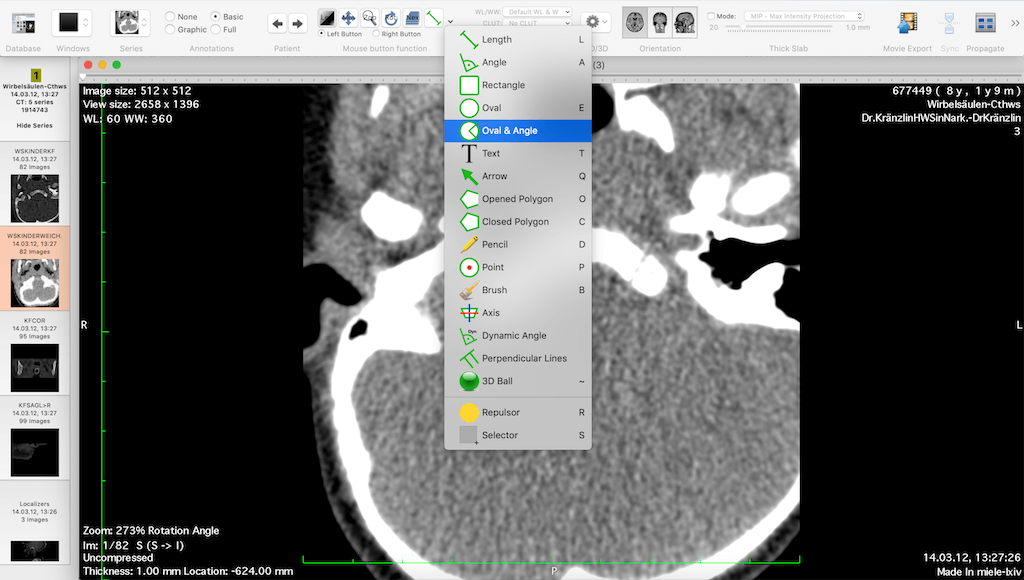

Horos is an open source DICOM viewer for Mac. It is actually the free version of an expensive DICOM viewer called Osirix MD, which is often considered to be the best DICOM viewer for Mac. It only runs on Mac OS, version 10.8 or higher. This software allows for most diagnostic techniques, including multiplanar reconstruction, maximum intensity projections, and volume rendering. It also has tools for manipulating images and making measurements.

One of the unique features of Horos is that it has a plug-in that allows uploading of images to Radiopedia, an online resource with a large number of reference cases and articles. Technical support is available through both phone and email. Horos, however, does not integrate to PACS free of cost. Cloud-based storage is available at an additional cost.

| 2. | Horos | Mac OS | Available for extra fee | Y | Y | Y | N.A. | N.A. | i5 processor/ 16 GB RAM | Open source |